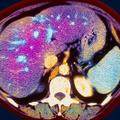

Pri nas Samo v enem dnevu dve resni zastrupitvi najstnic s paracetamolom Zastrupitev s paracetamolom je lahko tudi usodna, saj lahko povzroči jetrno okvaro ali celo popolno odpoved jeter.